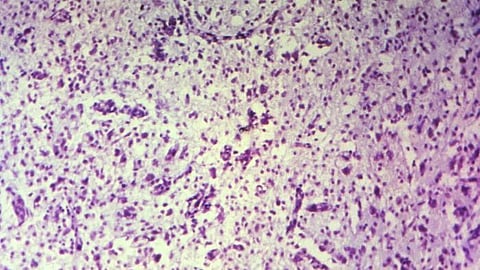

They found new sub-populations of GSCs that bear the molecular hallmarks of inflammation and which are commingled with other cancer stem cells inside patients' tumors. It suggests that some glioblastomas start to form when the normal tissue healing process, which generates new cells to replace those lost to injury, gets derailed by mutations — possibly many years before patients become symptomatic, Dirks said.

The data confirmed extensive disease heterogeneity, meaning that each tumor contains multiple sub-populations of molecularly distinct cancer stem cells, making recurrence likely as existing therapy is unable to wipe out all the different sub-clones.

A closer look revealed that each tumor has either of the two distinct molecular states – termed "Developmental" and "Injury Response" – or a gradient between the two. According to the researchers, the developmental state is a hallmark of the glioblastoma stem cells and resembles that of the rapidly dividing stem cells in the brain before birth.

But the second state came as a surprise. The researchers termed it "Injury Response" because it showed an upregulation of immune pathways and inflammation markers such as interferon and TNFalpha, which are indicative of wound healing processes. (SP/NewsGram)